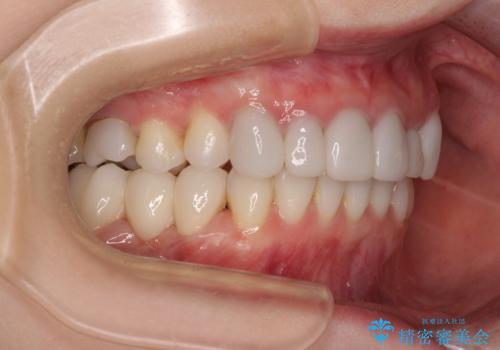

前歯のデコボコと奥歯の咬み合わせをインビザラインで改善

- 上下前歯のデコボコと奥歯の欠損を気にして来院された患者様です。

右下の欠損分は奥歯が倒れ込んでスペースがなくなっていたため、矯正治療により本来の位置に歯を移動させ、オールセラミックブリッジによる欠損補綴治療を行うこととしました。

全顎的にセラミッククラウンが多く装着されているため、インビザラインによる矯正治療を行うこととしました。

右下は移動量が多いため、十分な移動が達成されない場合はワイヤー装置を使用する予定としておりましたが、しっかりとマウスピースを装着してくださったため、前歯とともに十分に歯を動かすことができました。